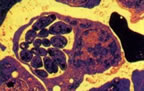

Protozoa alt filumunun eşadı. Özel bir hareket yönteminden yoksun, parazit hayvanlardır.

Bunlardan biri insanlarda parazit olup sıtmanın etkenidir.